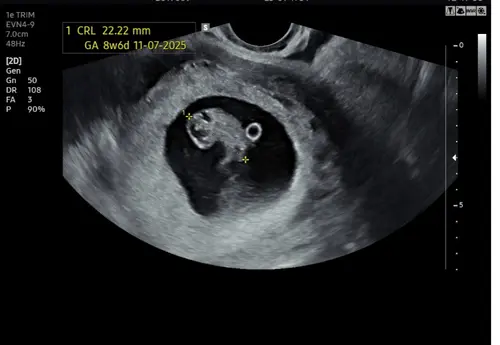

Ik dacht zelf 14 juli 2025, maar volgens de meting bij de 1e echo zou het ook 11 of 12 juli kunnen zijn. Termijnecho staat gepland voor 24 december, we wachten het af.

Wat een mooie echo 馃グ